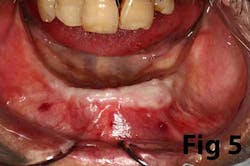

Gingival recession is the result of loss of alveolar bone and tissue, specifically AG. A high number of recession cases result in less than the minimum required amount of AG. (Fig. 4) Similarly, following tooth extraction or long-standing edentulism (without bone preservation), loss of alveolar dimension is accompanied with diminishing AG. (Fig. 5)Note: specific cases may also be attributed to gingival biotype and genetic predisposition.

Surgical reconstruction of a deficient ridge/site begins with bone augmentation (i.e., lateral ridge graft, sinus augmentation, etc.), closely followed by soft-tissue augmentation (i.e., onlay graft, pedicle graft, etc.) When either cannot produce adequate ridge form for esthetics, prosthetic solutions are used to compensate for this deficiency. Soft-tissue augmentation, particularly those procedures to increase AG, is often overlooked.